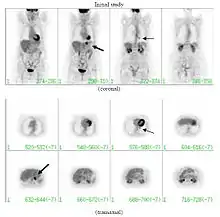

При среднем риске злокачественности, по возможности, проводится плановое ПЭТ-исследование (позитронно-эмиссионная томография). Приблизительно у 95 % пациентов со злокачественным новообразованием в лёгком ПЭТ-картина обнаруживает патологические изменения в лёгочной ткани; у 78 % пациентов с доброкачественным новообразованием ПЭТ-картина патологию не обнаруживает[7]. Таким образом, позитронно-эмиссионная томография надёжно выявляет злокачественные новообразования в лёгких, однако в ряде иных случаев (например, при воспалении, инфекционном процессе) патологический очаг также выявляется. При диаметре образования менее 1 см проведение ПЭТ не целесообразно в связи с повышенной возможностью ложно-отрицательного результата[7][8][9]. Злокачественные новообразования обычно имеют высокий метаболизм, что проявляется при ПЭТ высоким потреблением фтордезоксиглюкозы (ФДГ).